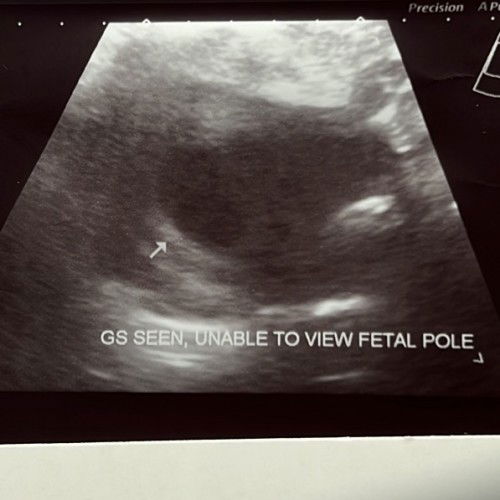

Normal or not?

hai mommies! nak tanya, normal ke 7week belum nampak fetal pole. btw, sorry bertanya sbb anak first 🥰 nak tahu jawapan mommies berpengalaman jugak ❤️